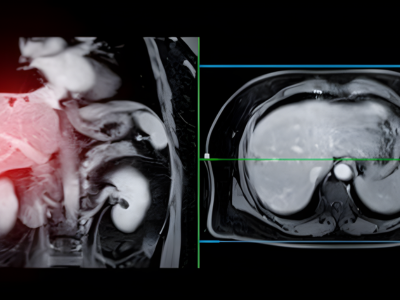

MRI with Liver-Specific Contrast

Provides high-resolution imaging, enabling the thorough assessment of liver lesions and vascular structures as well as liver function to assist interventions such as radioembolization.